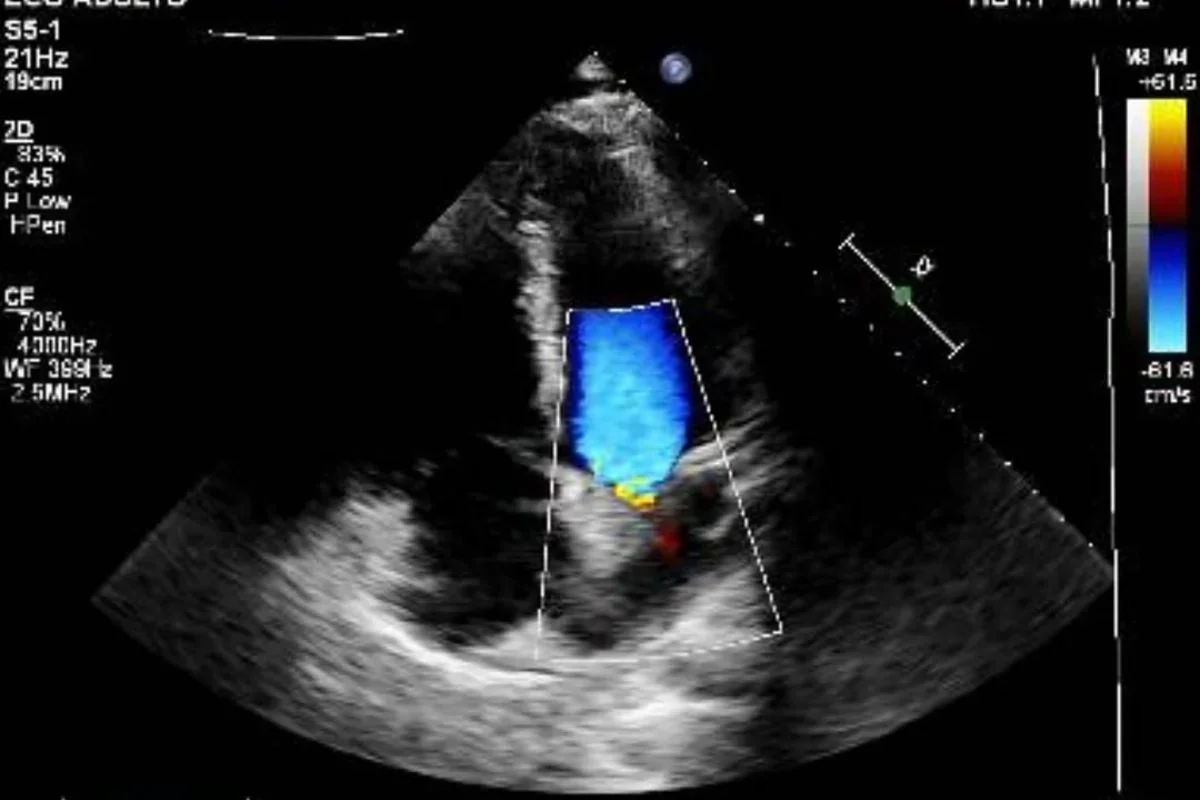

Vittor descreveu o episódio como os dias mais apavorantes de sua vida e disse ter sentido a morte muito próxima. Ele publicou fotos no hospital, imagens do carro atingido e exames que mostram o projétil alojado. Além do ferimento no peito, ele também foi baleado na perna.